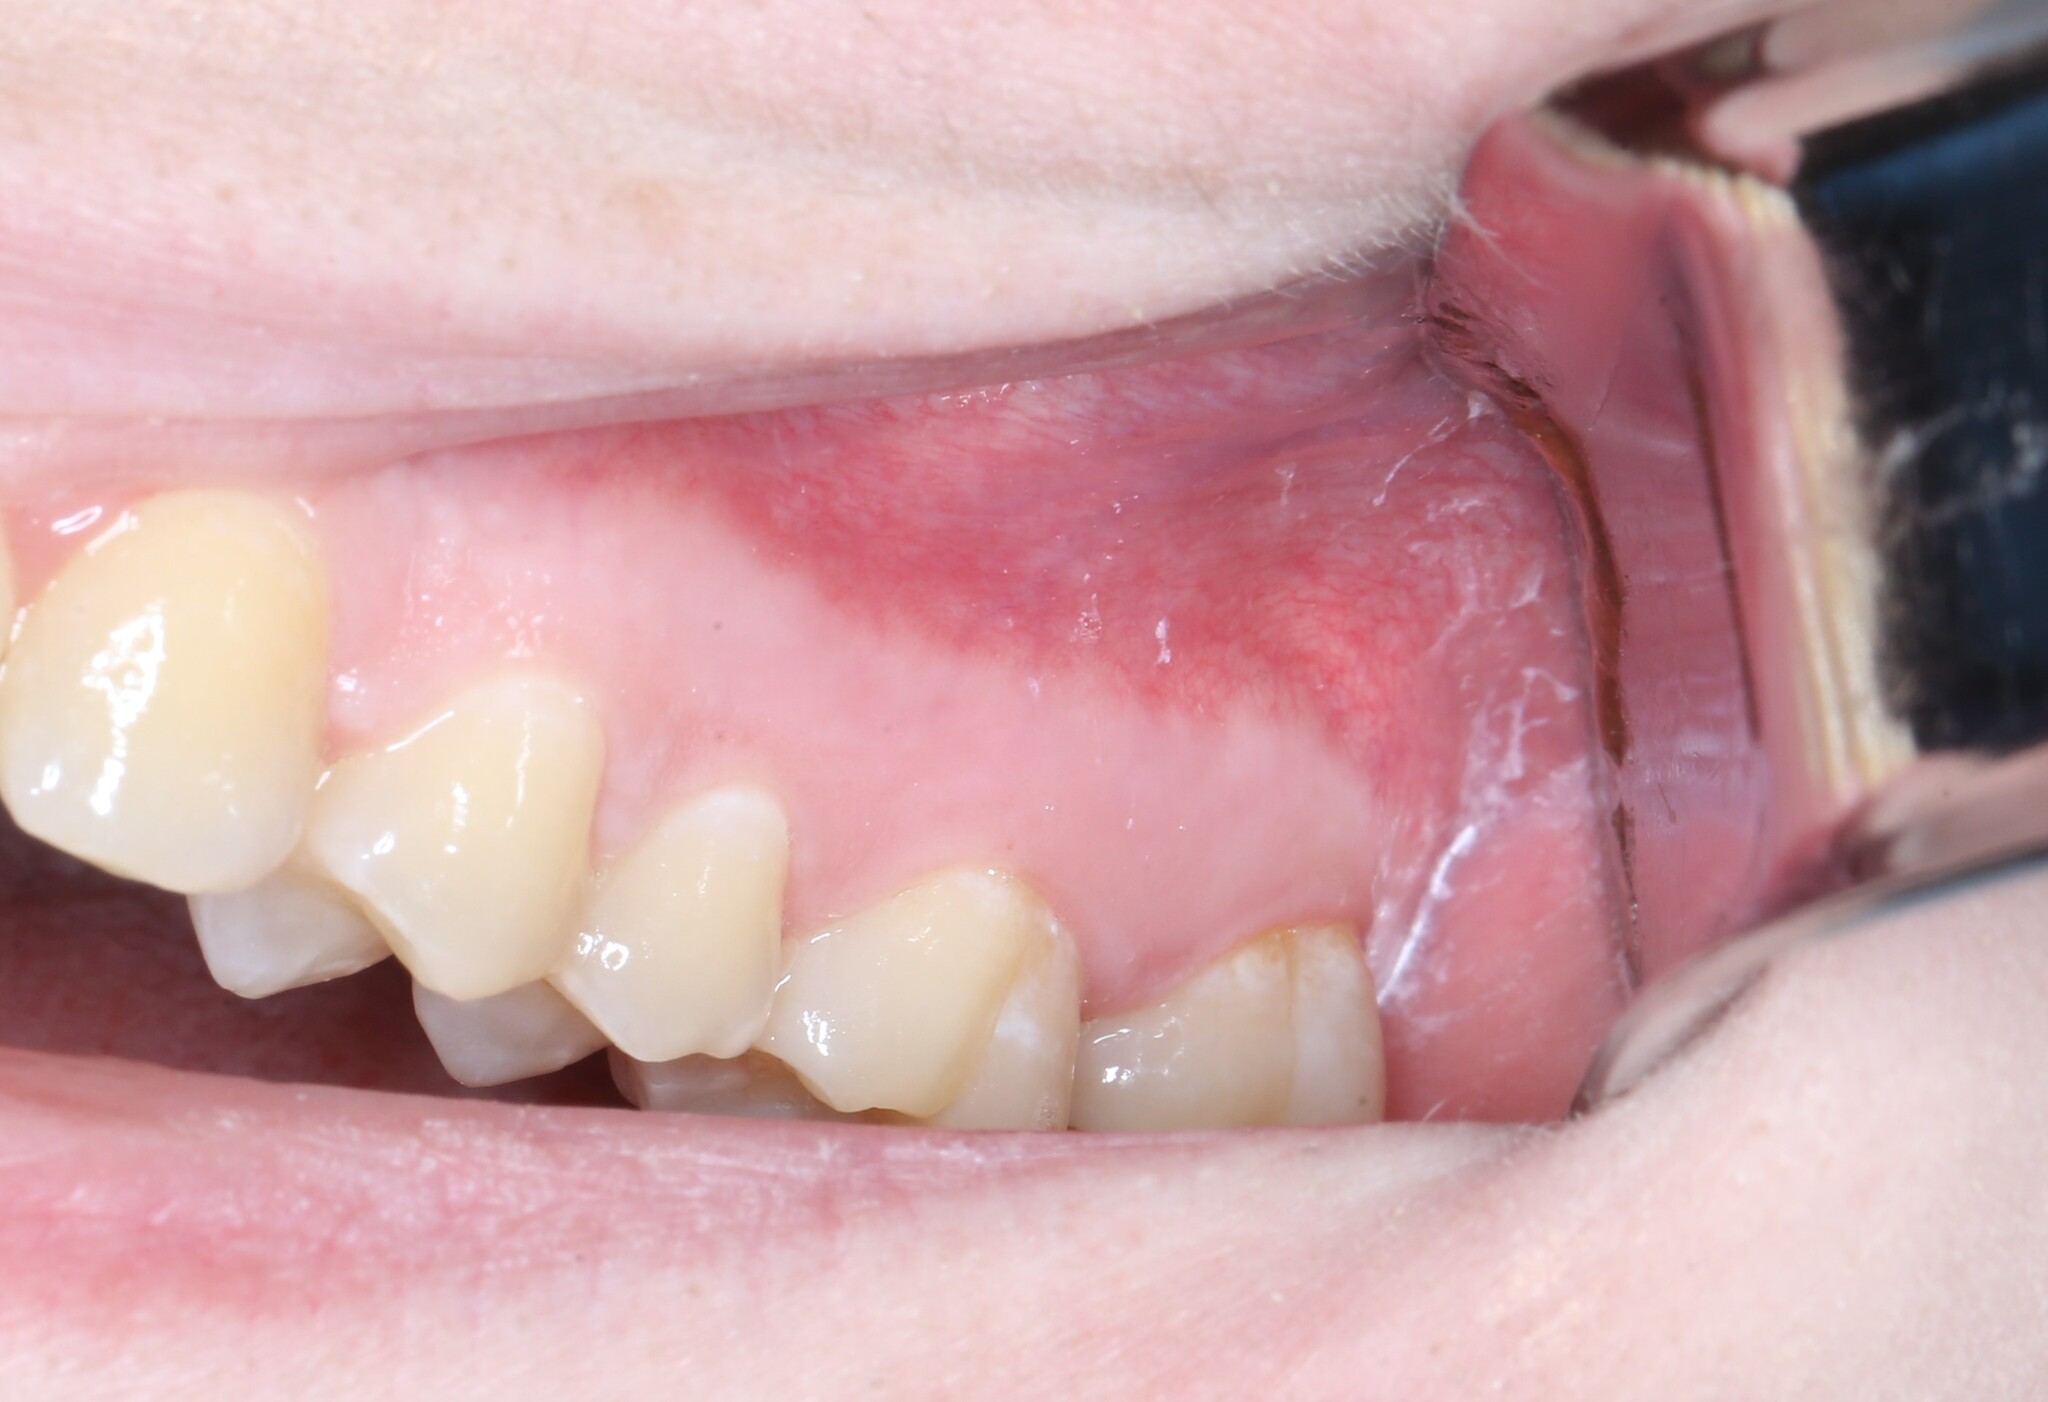

Вот так выглядит область, в которую мы планируем вмешаться: